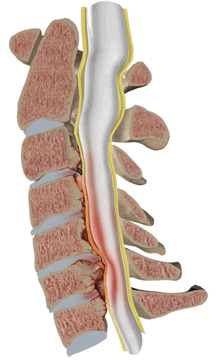

Стеноз (сужение) просвета позвоночного канала со сдавлением спинного мозга с гипертрофией задней продольной и жёлтой связки.

Также к сужению позвоночного канала приводят гипертрофия желтой и задней продольной связок, увеличение толщины суставных капсул межпозвонковых суставов, смещения межпозвонковых дисков и фиброзного кольца, участвующих в формировании позвоночного канала.

Сужение позвоночного канала в переднезаднем направлении может быть обусловлено его вторичным стенозом, гипертрофией задней продольной и жёлтой связки, спондилолистезом. Для установления стеноза позвоночного канала необходимо измерение канала в сагиттальной плоскости. Абсолютным стенозом принято считать уменьшение диаметра канала до 10 мм и менее. Величина в 10-15 мм соответствует частичному стенозу. Толщина задней продольной связки в норме не должна превышать 2 мм, желтой связки — 3 мм.

Стеноз позвоночного канала со сдавлением спинного мозга при спондилёзе на уровне шейного отдела позвоночника с гипертрофией задней продольной и жёлтой связки.